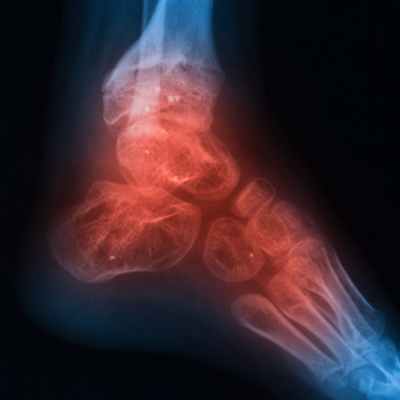

Остеомиелит – это тяжелый инфекционно-воспалительный процесс, поражающий все элементы кости. Под термином «остеомиелит» в настоящее время понимают неспецифическое гнойное или гнойно-некротическое поражение костной ткани (остит), костного мозга (миелит), надкостницы (периостит) и окружающих мягких тканей.

Рентгенологическое исследование считается одним из наиболее эффективных методов диагностики остеомиелита. Признаки патологии у детей видны на снимке уже на 5-й день, а у взрослых — только через 2 недели от начала воспалительного процесса.

При попадании инфекции в кость первым страдает мягкое вещество (костный мозг). Воспалительный отек провоцирует микроциркуляторные нарушения, из-за чего патологические изменения распространяются на другие слои костей. В костной ткани образуются гнойно-некротические очаги. Возможно формирование абсцессов и свищей, которые открываются через кожу. Инфекция способна распространяться в другие органы и ткани, провоцируя в них воспаление и гнойные изменения.

Распознавание. Рентгенологическое исследование ценно для определения локализации и протяженности очага поражения, помогает установить характер имеющихся патологоанатомических изменений. Первые рентгенологические симптомы начинают выявляться с 10-14 дня заболевания. В ряде неясных случаев целесообразно применение томографии. При хроническом остеомиелите, протекающем с образованием свищей, важное место занимает фистулография. Она позволяет уточнить локализацию секвестра и выявить, когда обычные снимки оказываются недостаточно четкими. При фистулографии применяют контрастные вещества (йодолипол, сергозин, диодон и др.). Наиболее точно зону поражения кости удается определить методом радиоактивного сканирования с применением радиоактивного технеция, что чрезвычайно важно для решения вопроса об объеме операции.